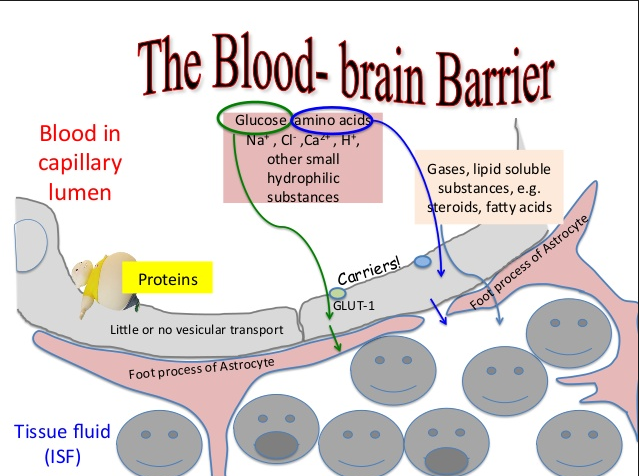

Heme | definition of heme by Medical dictionary

Heme binds and carries oxygen in the red blood cells, releasing it to tissues. Also spelled haeme. See also hemoglobin, porphobilinogen, protoporphyrin.

Heme | definition of heme

Heme | definition of heme OUTPUT formats

Heme | definition of Theme …. SCheme